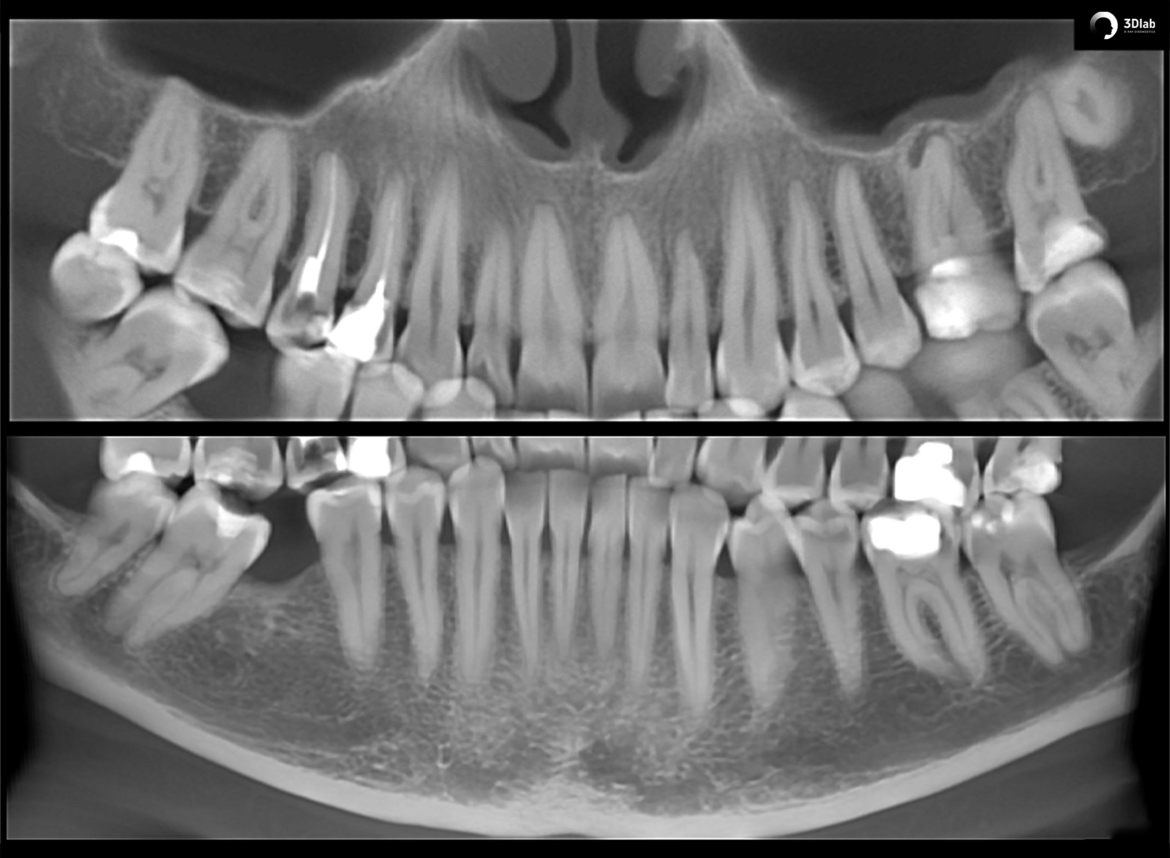

КЛКТ здесь https://3dmedica.ru/ – это современный метод изучения зубов и окружающих их тканей, который позволяет получить трехмерное изображение зубочелюстной системы с высоким разрешением. Этот инновационный подход в диагностике стоматологических проблем играет ключевую роль в точном определении патологий, планировании лечения и проведении хирургических вмешательств.

- Высокое разрешение. Благодаря высокой четкости изображения, КЛКТ позволяет точно увидеть структуру зубов, корней, костей челюсти и окружающих тканей, что делает его незаменимым инструментом для диагностики различных зубных заболеваний.

- Точность диагностики. С помощью КЛКТ специалист может обнаружить проблемы, которые могут остаться незамеченными на обычных снимках рентгена, например, скрытый кариес, очаги воспаления или нарушения структуры корней зубов.